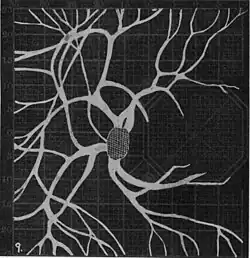

Angioscotomas were first discovered and mapped out by John Norris Evans (1891-02-28--1953-04-08)[2] in 1926, who coined the term angioscotometry to describe the painstaking charting of the scotoma of the retinal blood vessels by manual perimetry. He seated each subject in a seat in a dark setting, and tested whether they could see a tiny bright test object placed at various locations.[3] Using a 1.5 mm white disk, Evans reported intricate branch‑like scotomas that mirrored the arteries and veins emerging from the optic disc, with a full map requiring up to 2 hours to complete. He plotted this for subjects under various conditions, such as while holding breath, with glaucoma, etc. A year later, he confirmed that only short stump‑like scotomas had been noticed previously, some further data plotted with a smaller 1 mm stimuli, and under varying conditions on the subject.[4] He published a monograph on this in 1938 in which he described its use in assisting diagnosis of various conditions, such as retinal edema, glaucoma, optic neuritis, etc.[5]

In the 1940s there were further developments. Evans reviewed the state of research in 1942.[6] In 1945, Welt designed a portable campimeter and linked the size of both the blind spot and the angioscotoma to retinal arterial pressure.[7] In the same year, Weekers and Humblet published detailed tracings that overlaid vessel photographs onto Bjerrum screen plots, firmly establishing the one‑to‑one correspondence between vascular anatomy and scotoma shape.[8]

20. Venous engorgement. 21. After pressure over internal 22. Same case, normal. 23. Scotoma after ligation of common carotid. 24. Edematous swelling of nerve and retina. 25, Normal blind spot of other eye. -

Widening of angioscotoma under various conditions (holding head lower than trunk; holding the breath; making digital pressure on the same eye; (a vein) on opposite eye; (an artery) on opposite eye).